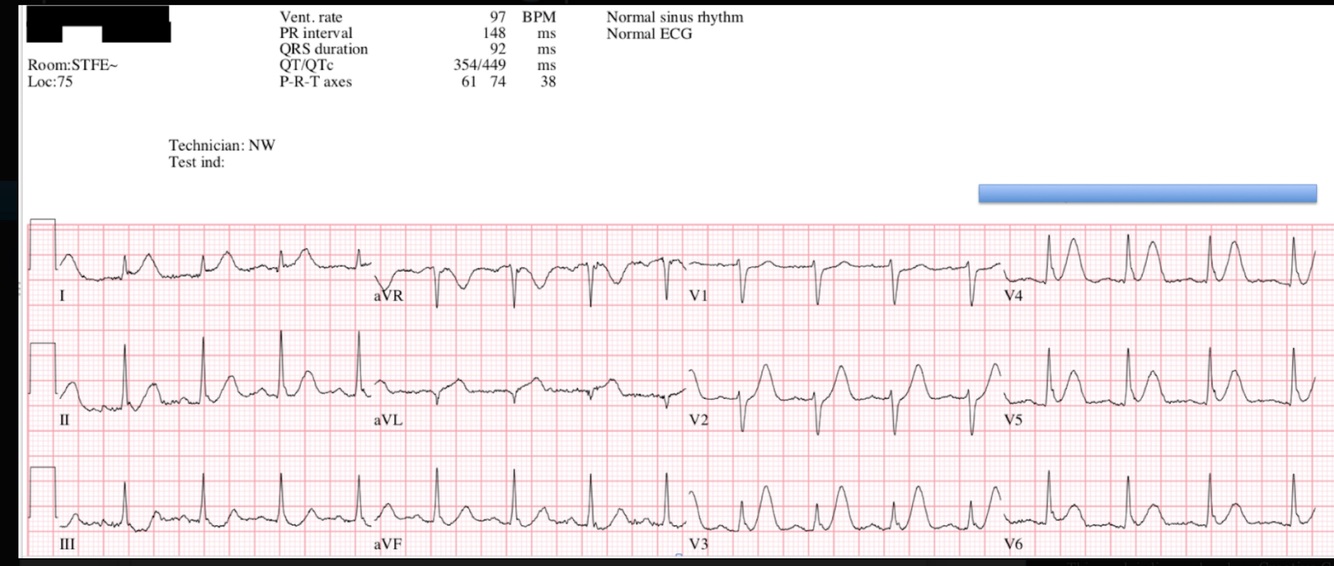

Hyperacute T-waves - Inferior 2

Broad, asymmetrically peaked or ‘hyperacute’ T-waves seen in early stages of MI.

Disproportionately increased area under the ST segment and T wave compared to the QRS

“Inflating the T-wave like a balloon”